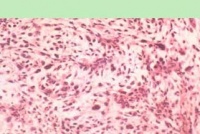

镜下其稠密的细胞区与稀疏的细胞区和粘液样改变区,三者可交替出现。另一恒定不变的特征为细胞分布无规律,同时其中的网状及胶原纤维非常稀疏。未分化的细胞形体小,具有圆或椭圆的核,染色深。随着分化的进展,出现典型的巨大单核细胞胞核增大,具有空泡及大的

横纹肌肉瘤

核仁胞浆嗜曙红性强,且呈颗粒状,胞核周围有极丝,还可看到横纹。分化差的细胞呈球形,胞核周围有一薄的胞浆环。进一步分化胞浆愈加充实,核呈偏心性,很多有丝分裂相,形状像“蝌蚪”或“球拍”,再分化后变为带状物,有时细胞可伸长呈角状。在这些细胞中可见到横纹,有些细胞可出现放射状丝状物,形成蜘蛛网样细胞。肿瘤的其余部分为侵袭状态的梭形细胞混杂,有明显的血管形成和较多的有丝分裂相,有时可有肿瘤细胞团和侵袭较大的内皮胞间隙

腺泡样横纹肌肉瘤由未分化的小圆形—卵圆形细胞所组成,并聚集成为实质性的小岛或小泡,小岛和小泡被粗糙的稠密胶原带分离,含有扩大的毛细血管。多形性横纹肌肉瘤是一种具有球形细胞、梭形细胞、巨细胞和球拍状及蝌蚪样细胞的多形性肿瘤,胞浆中很少看见横纹。

(2)组织病理:在黏液基质中存在圆形或梭形细胞。核呈圆形或卵圆形染色质疏松,核仁不清,胞质丰富而红染。当核偏于细胞一侧时,常呈蝌蚪状。有时在梭形细胞内可看到纵纹或横纹。

(2)组织病理:窄的结缔组织小梁将肿瘤细胞分隔成腺泡样,有一或数层肿瘤细胞附着于小梁上,中央空腔内漂浮有少数肿瘤细胞。可见大的多核细胞,其间可见横纹或纵纹。以前的描述着重于腺泡样结构,更强调于肿瘤细胞的巨核、多形性及粗的染色质。细胞遗传学上存在t(2;13)(q35;q14)异位,对其断裂区的分析可与Ewing氏肉瘤鉴别。

(2)组织病理:基本上是梭形肿瘤细胞,具有多形性可见到长

形带状细胞,胞质丰富,染为鲜红色,胞质内可见到横纹,即肌纤维。此外,可见不典型星状细胞,核分裂相多见;圆形细胞,胞质强嗜伊红性,有时核偏位;管柱形细胞,肌原纤维位于包膜下方,中央区淡染,核圆,单个或多个,可见核周空晕;梭形细胞多见,细胞的长短粗细不一,胞质丰富淡嗜酸性染色,常含肌原纤维,并可见各种形态的多核细胞。